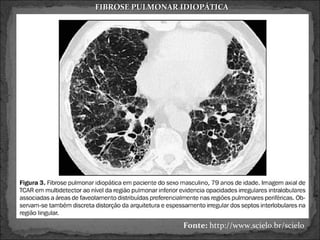

 TCAR

 Extensão do acometimento pulmonar e fase da dça.

 Precoce: áreas em vidro fosco

 Avançada: faveolamento

Fonte: http://www.scielo.br/scielo